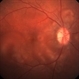

- preeclampsia, choroidal infarction

- Imaging device

- Fundus camera

- 66-year-old Hispanic female with a history of severe preeclampsia at age 45. This photograph shows faint gray choroidal scars. Seen better on FA (in gallery).